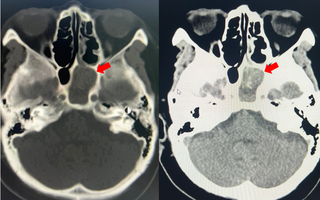

Viêm xoang bướm do nấm âm thầm tấn công người bệnh

(NLĐO ) - Bệnh viêm xoang bướm do nấm có triệu chứng mơ hồ, không điển hình, dễ nhầm với viêm xoang mạn thông thường.